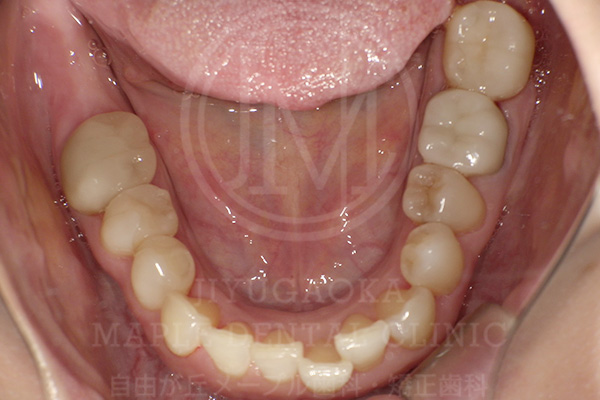

銀歯を外してセラミック治療にした症例

case1

治療前

治療後

| 治療内容 | 古い銀歯をセラミックに治療 |

|---|---|

| 治療期間 | 約8ヶ月 |

| 治療費用 | 792,000円(8.8万円×9本)(税込) |

| 治療後に起こりうるリスク | 個人差により、ごく稀に欠けたり壊れる可能性があります |